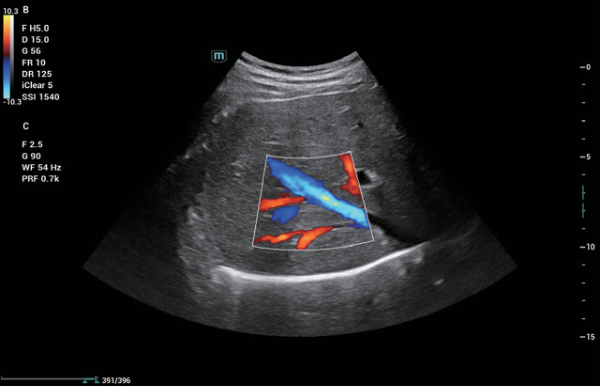

A linha Consona apresenta solu??es inovadoras e eficientes que o ajudam a realizar diagnÃģsticos em diversos tipos de pacientes.

N?o importa se sua rotina ÃĐ em hospitais, clÃnicas ou se vocÊ estÃĄ aprimorando habilidades em Imagem Geral, SaÚde da Mulher ou na ÃĄrea Cardiovascular; vocÊ encontrarÃĄ ferramentas altamente poderosas disponÃveis para manter-se na vanguarda.

Solu??es abrangentes de imagens com tecnologia ZST+

A plataforma ZST+ ÃĐ uma inova??o extraordinÃĄria, representando a evolu??o do ultrassom. Transformando as mÃĐtricas de ultrassom: da forma??o convencional do feixe ao processamento baseado em dados de canais. Supera a limita??o de compensa??o tradicional entre resolu??o espacial, resolu??o temporal e uniformidade de tecido, oferecendo qualidade de imagem excepcional para solu??es de imagem infinitas com melhorias inigualÃĄveis.